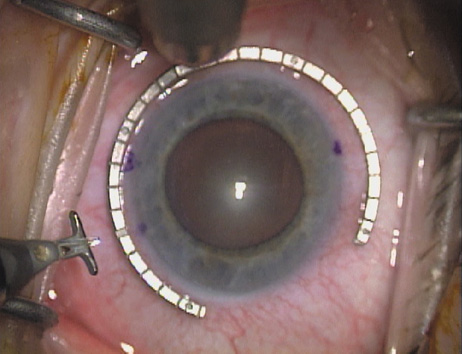

As noted, in the setting of concomitant cataract surgery, an empiric blade

depth setting of 600 microns is commonly employed. Various knives

have been designed specifically for this application, ranging from disposable

steel blades to exquisite gemstone diamond knives. Synthetic (and

less expensive) diamond materials are also available and

are intended for limited reuse. Our preference is for diamond blade technology

that incorporates a single small and arced footplate for enhanced

visualization at the limbus (Mastel Precision). Two models

are available, one with a preset depth of 600 microns and the other

with an adjustable micrometer handle (Fig. 6). Similar designs are available from Rhein Medical, Storz, ASICO, and

other manufacturers.   Fig. 6. (A)A diamond blade with a preset depth of 600 microns is used

to perform LRIs for routine cataract surgery. (B) An adjustable

depth micrometer blade is used in conjunction with the NAPA nomogram

when treating younger patients. Fig. 6. (A)A diamond blade with a preset depth of 600 microns is used

to perform LRIs for routine cataract surgery. (B) An adjustable

depth micrometer blade is used in conjunction with the NAPA nomogram

when treating younger patients.

|